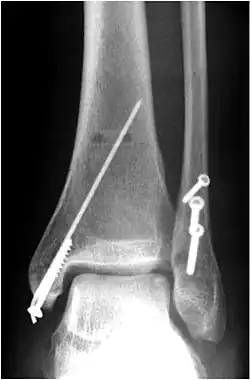

Osteosynthese der Fibula

Bei allen anderen Brüchen mit verschobenen Knochenbruchstücken und bei Verletzung der Gabelbänder ist in der Regel eine offene Operation mit Knochenverschraubung (Osteosynthese) und Bandstabilisierung notwendig. Die einfachste und biomechanisch stabilste Versorgung erfolgt mit mindestens zwei bis drei Zugschrauben je nach Länge der Schrägfraktur des Wadenbeins (Abb.). Alleinige Schraubenosteosynthesen sind nur bei einfachen Spiral- oder Schrägbrüchen möglich, Mehrfragmentbrüche werden mit Einzelschrauben zu größeren Fragmenten vereinigt, die dann mit einer Platte stabilisiert werden, die längs auf das Wadenbein verschraubt wird. Im anderen abgebildeten Fall kam eine Zugschraube und eine 6-Loch-1/3-Rohrplatte als sogenannte Neutralisationsplatte am Außenknöchel und eine Zuggurtung am Innenknöchel zum Einsatz. Beide Versorgungen sind übungsstabil, auf eine Gipsruhigstellung kann verzichtet werden. Der Patient darf mit leichter Kontaktbelastung an Unterarmgehstützen gehen.

Osteosynthese des Innenknöchels

Meist handelt es sich bei der Innenknöchelfraktur um eine Abrissfraktur. Eine konservative Behandlung ist hier nicht möglich. Daher muss der Innenknöchel über einen Längsschnitt freigelegt werden. In den Bruchspalt ist immer die Knochenhaut eingeschlagen, was eine anatomische Reposition behindert. Nach Beiseiteschieben des Periosts kann die Fraktur einfach anatomisch reponiert werden. Das Fragment wird mit Bohrdrähten oder mit Bohrdraht und Zugschraube fixiert (Abb.). Selten besteht das Innenknöchelfragment aus mehreren Teilen, die durch mehrere Drähte und gegebenenfalls auch eine Drahtcerclage fixiert werden können. Eine Schraubenfixierung ist bei solchen Mehrfragmentbrüchen nicht möglich.